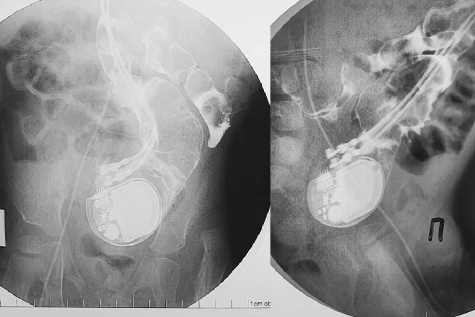

Однако спустя три года кардиостимулятор мигрировал в кишечник. При этот устройство продолжало исправно работать. Но отрыв или инфицирование электродов аппарата могли привести к гибели малыша. Кроме того, у ребенка уже образовался кишечный свищ, возникла закупорка кишечника.

К счастью, кардиохирургам Мешалкина и хирургам областной больницы удалось успешно извлечь кардиостимулятор из кишечника и имплантировать новый аппарат в грудь. По словам специалистов, такая ситуация с устройством впервые в практике российских врачей.